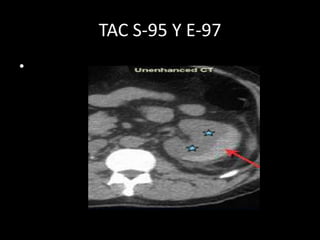

TAC S-95 Y E-97

•

TAC S-95 YE-97 •